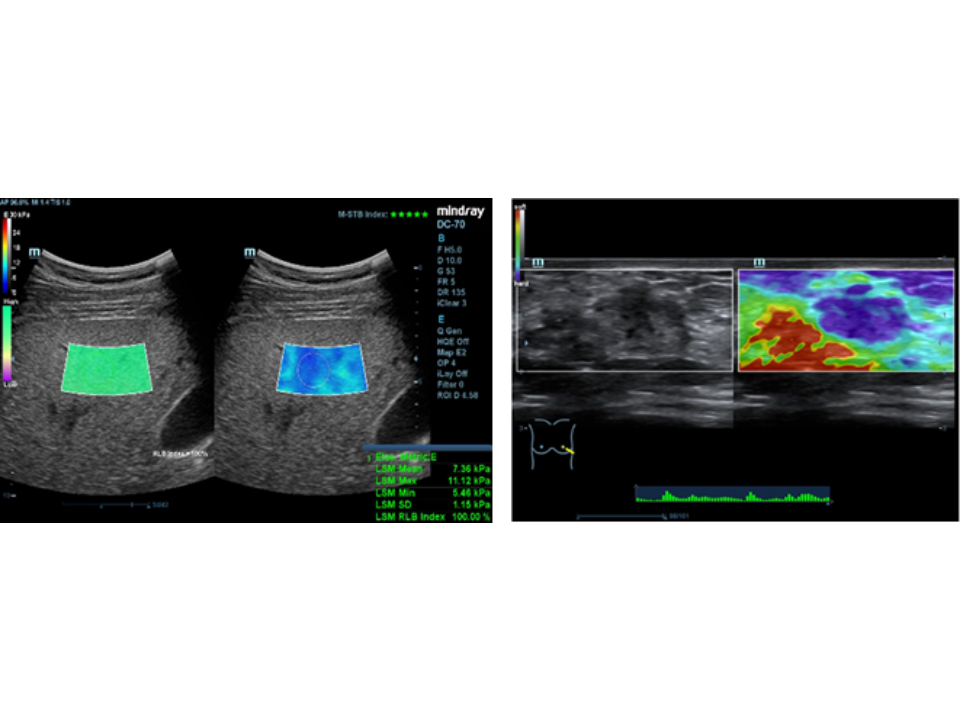

Clinical Images